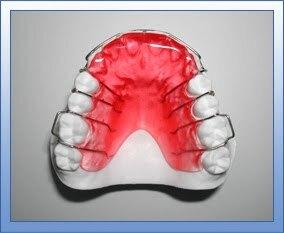

②Hewley's retainer(沒啥固定中文譯名,有人叫哈雷維持器,有人叫有鐵絲的那種維持器,有人叫活動式維持器....)

Hewley's retainer

哈雷維持器

哈雷維持器在石膏模型上

上顎維持器是Hewley's retainer,下顎維持器是wrap around retainer(詳細介紹在文末FAQ 2)

此為邱醫師的個人習慣,通常上下形式都一樣 ,